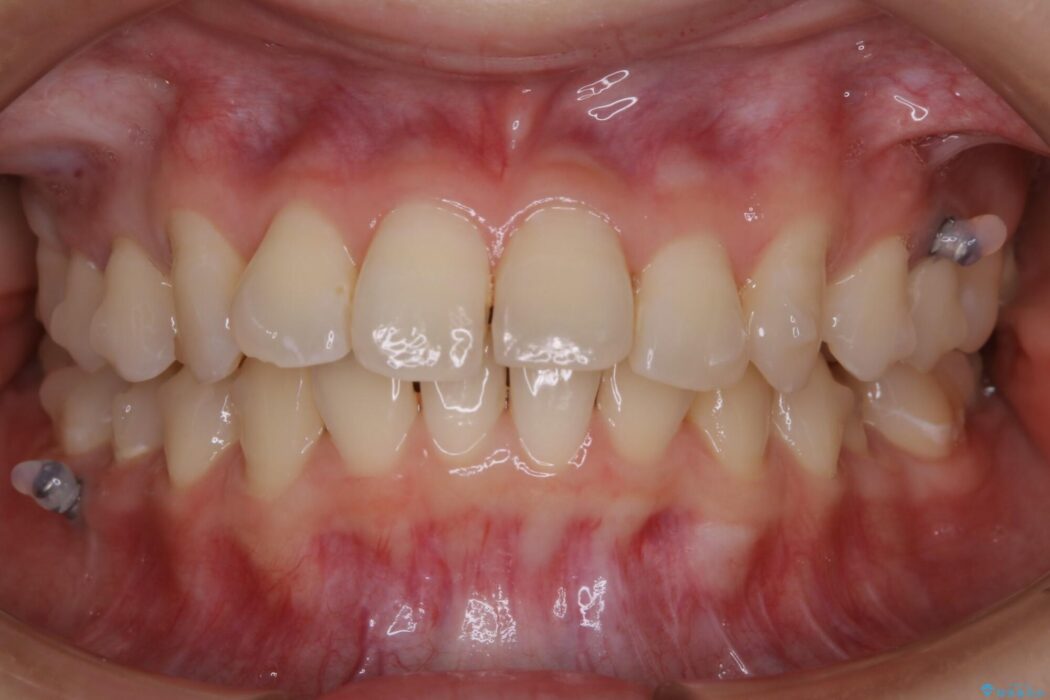

【20代女性】ブライダルに向けた矯正できれいなスマイルラインへ

笑った時に見える歯並びをきれいにしたいとの主訴で来院されました。

ガタつきの度合いから抜歯は不要と判断しましたので、マイクロインプラントを用いて歯全体を遠心移動させていくことでねじれや噛み合わせのズレを改善していく計画を立てました。